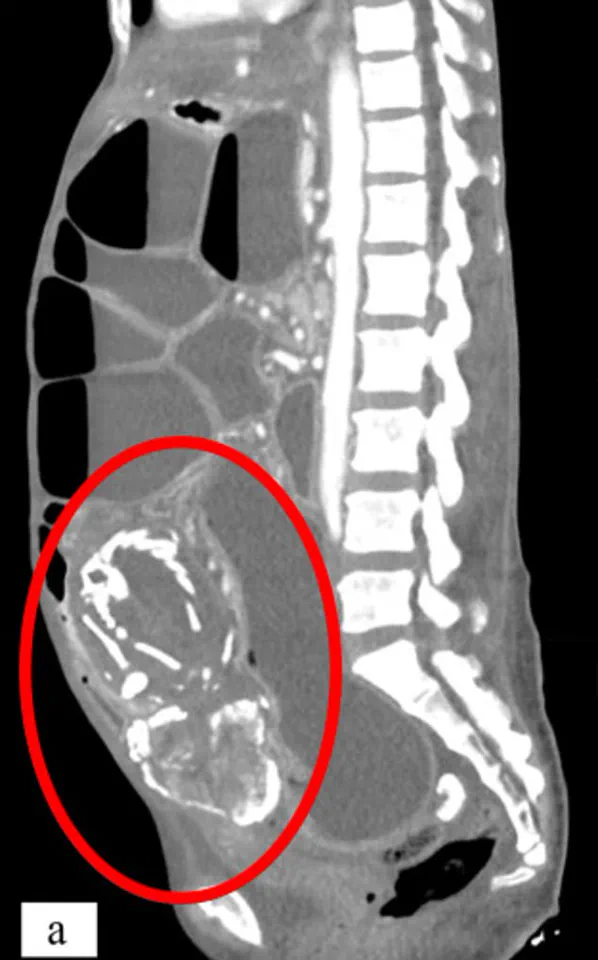

Last week's episode of *Call The Midwife* brought a rare and heartbreaking medical condition into the spotlight, highlighting a phenomenon known as lithopedion, or 'stone baby.' The storyline, set in the 1970s, depicted a woman experiencing unexplained pain and incontinence, only for surgeons to discover a calcified fetus embedded in her abdomen during a procedure. This condition, though fictionalized in the drama, is rooted in real medical history and has been documented in hundreds of cases worldwide.

Lithopedion is a rare complication of ectopic pregnancy, where a fertilized egg implants outside the uterus, typically in the fallopian tubes. When such a pregnancy fails, the body's immune system often reabsorbs the tissue. However, if the fetus survives beyond 12 weeks, its skeletal structure begins to calcify, forming a hard, stone-like mass. This process, a form of mummification, protects the mother from infection while leaving the calcified fetus trapped in the abdominal cavity for years, even decades.

Historical records show the earliest known lithopedion dates back to 1100 BC, uncovered during an archaeological dig in Texas. Modern cases, however, remain rare, with only 330 documented globally. Dr. Lee notes that advances in prenatal care and imaging technology have made lithopedion even rarer today. Early detection through blood tests and ultrasounds allows for timely intervention, preventing the calcification process from occurring.